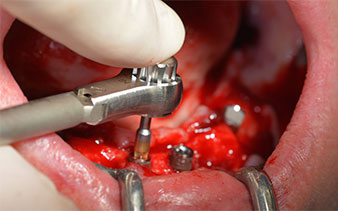

The mental foramen was first identified as a limiting anatomical structure and then the cortical bone of the crest was smoothed with the straight handpiece and a large rose-head bur (Fig. 4).

This is where the first advantages of Implantmed become obvious. The surgical protocol is already preset and the settings stored at fixed positions. The individual positions can be selected by simply pressing the “P” position on the foot control or via the display itself. The preset speed of 35,000 rpm in position 1 in this case is also shown in large figures on the illuminated display (Fig. 5 and 6).